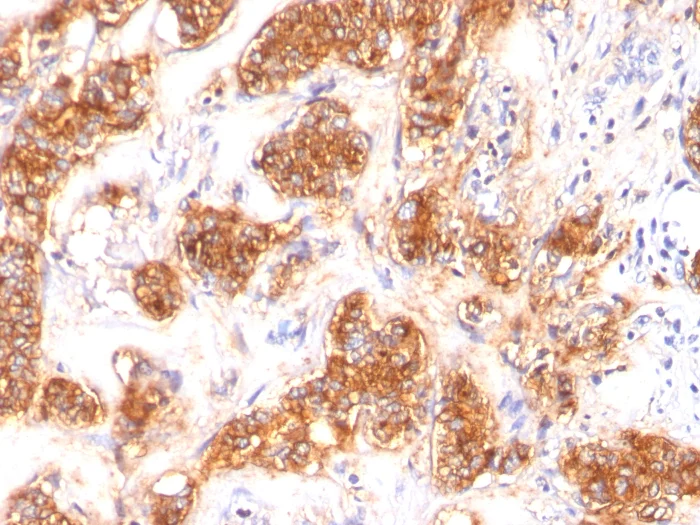

Immunohistochemistry (Formalin/PFA-fixed paraffin-embedded sections) - Anti-Milk Fat Globule 1 antibody [SPM291] (AB17787)

IHC image of ab17787 staining in human carinoma breast formalin fixed paraffin embedded tissue section, performed on a Leica BondTM system using the standard protocol F. The section was pre-treated using heat mediated antigen retrieval with sodium citrate buffer (pH6, epitope retrieval solution 1) for 20 mins. The section was then incubated with ab17787, 1μg/ml, for 15 mins at room temperature and detected using an HRP conjugated compact polymer system. DAB was used as the chromogen. The section was then counterstained with haematoxylin and mounted with DPX.

For other IHC staining systems (automated and non-automated) customers should optimize variable parameters such as antigen retrieval conditions, primary antibody concentration and antibody incubation times.